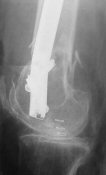

- Your last posted case: how is possible to have secure fixation with applied construct without additional casting, bracing or Ilizarov?

THX, initial images are

1,

2.

At that moment we had in stock only the 10 mm solid nails so of course there was no idea about early weight bearing. But it was quite enough for early knee ROM excersises (see attached). Two locking screws through the distal block provided that.